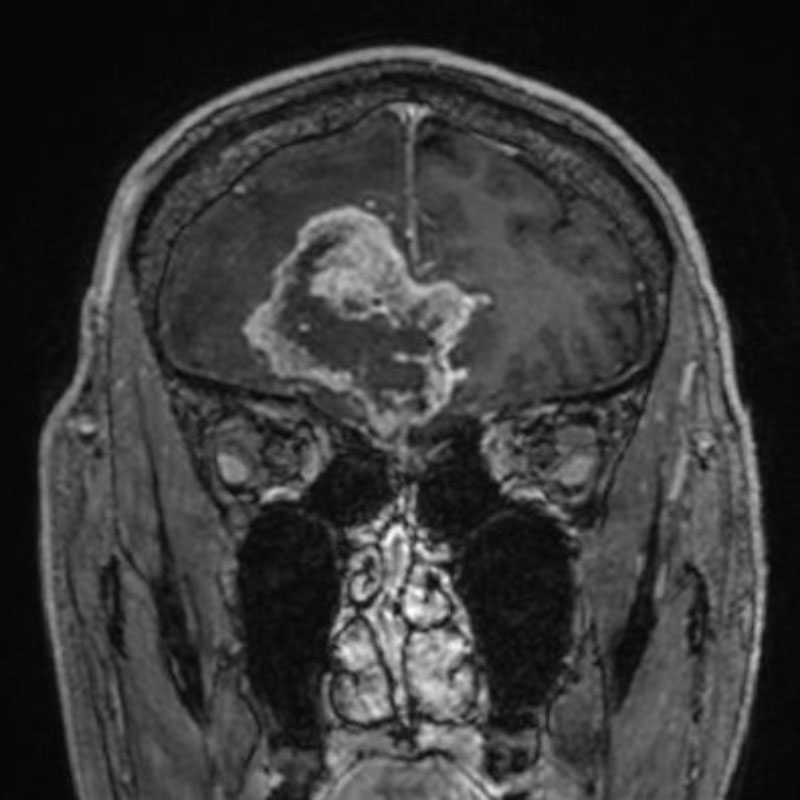

707

'25年12月

80代

髄膜腫

頭蓋内腫瘍摘出術

No.’25_109 手術前1

No.’25_109 手術前2